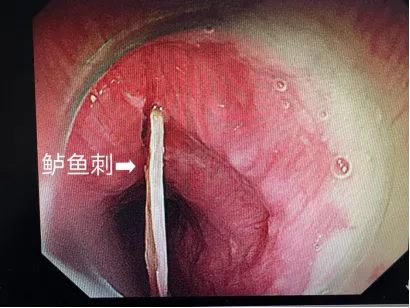

一位患者被鲈鱼刺横卡食管,若不及时处理,极易刺破血管、造成大出血。